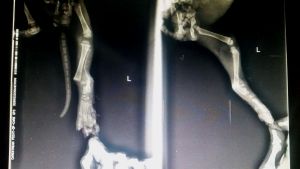

Linus wurde in einem ganz schlechten Zustand auf der Straße gefunden. Er ist extrem verschnupft, bekommt kaum Luft, die Lunge ist angeschlagen und er hat noch einen heftigen Bruch am Beinchen.

Die Tierschützer haben ihn sofort in die Klinik gebracht. Dort muss er erstmal stabilisiert werden, bevor die Operation gemacht werden kann. Momentan sieht es so aus, als wenn das Beinchen amputiert werden muss.